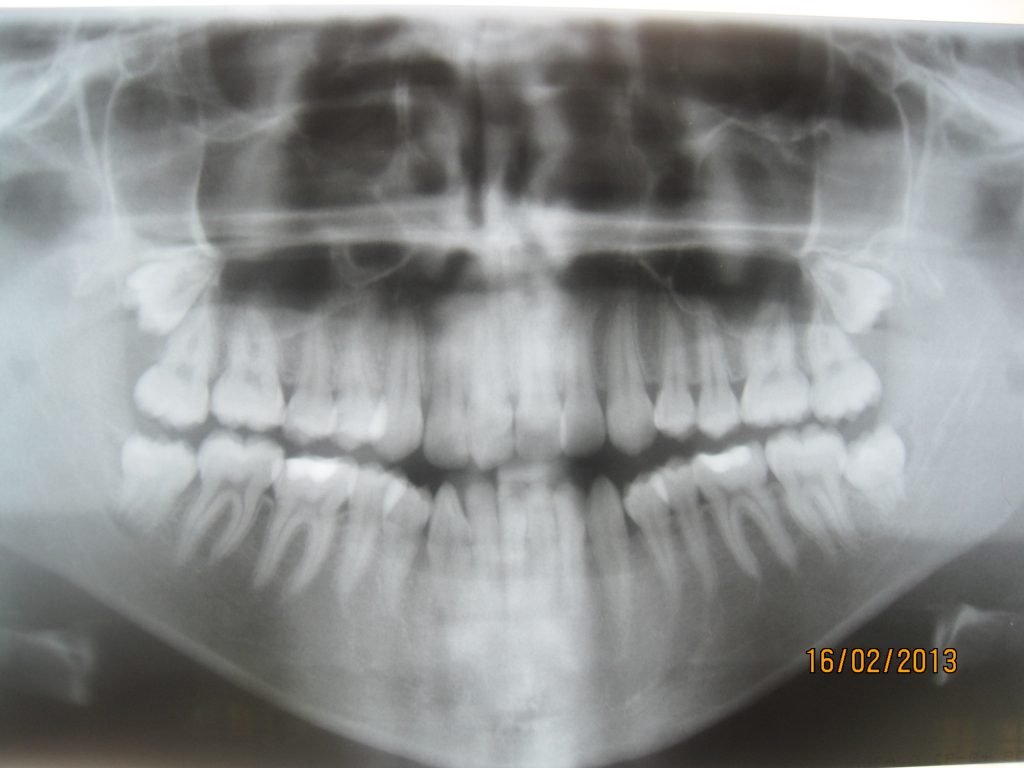

Streszczenie: W artykule został przedstawiony przypadek pacjentki z wadą gnatyczną typu progenia, która została poddana kompleksowemu leczeniu we współpracy z chirurgiem szczękowo-twarzowym w celu poprawy profilu tkanek miękkich, relacji zębowo-zębowych, wyrostkowych oraz szczękowych.

Summary: The article presents the case of a patient with prognathism of the mandible; she has undergone complex treatment in cooperation with a maxillofacial surgeon to improve the soft tissue profile, the dento alveolar profile and the correlation between soft and hard tissue.